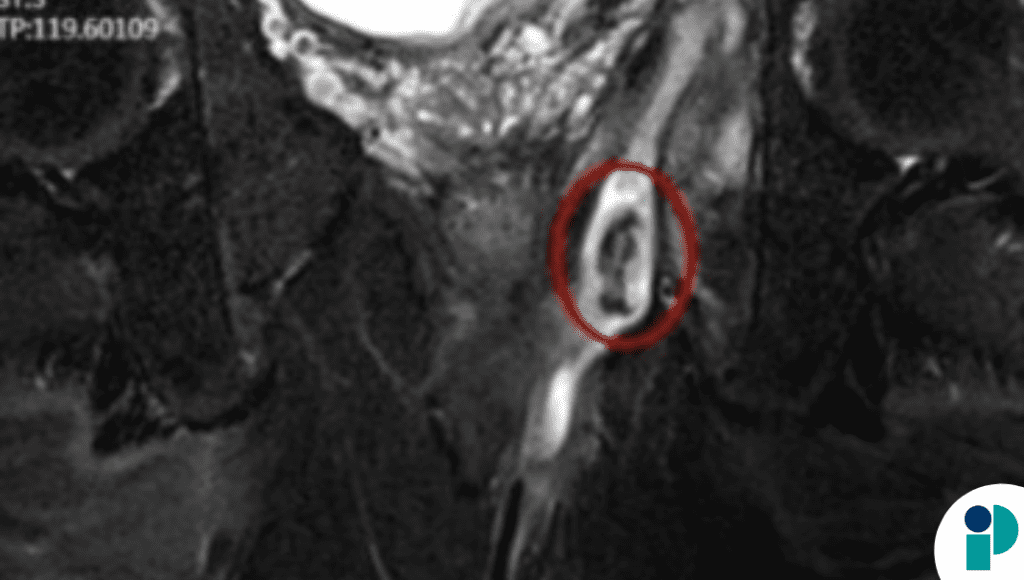

Al ser referido a un centro especializado, el hombre consultó por dolor perianal, secreción purulenta e incontinencia fecal líquida. Una resonancia magnética pélvica reveló un absceso en la fosa isquiorrectal izquierda, con un foco central de baja señal sugestivo de un cuerpo extraño, así como un trayecto fistuloso anal alto. Ante estos hallazgos, se decidió realizar una cirugía transesfintérica.